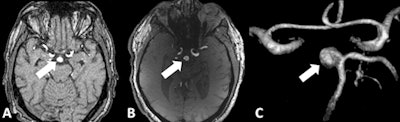

The researchers found that 7-tesla TOF MRA provided significantly superior delineation of the dome and neck, compared with 1.5-tesla MRA.

"In our study, we were able to improve the spatial resolution to a minimum voxel size of 0.2 x 0.2 x 0.4 mm3 at 7 tesla, instead of 0.35 x 0.35 x 0.7 mm3 at 1.5 tesla," Umutlu explained. "Based on this superior spatial resolution, as well the improved vessel-to-tissue contrast, 7-tesla TOF MRA allowed for a significantly improved delineation of the intracranial aneurysms."